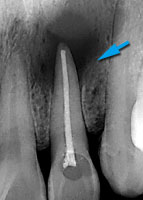

虫歯が神経まで進行してました。

神経を抜いた後、根尖まで緊密に充填します。